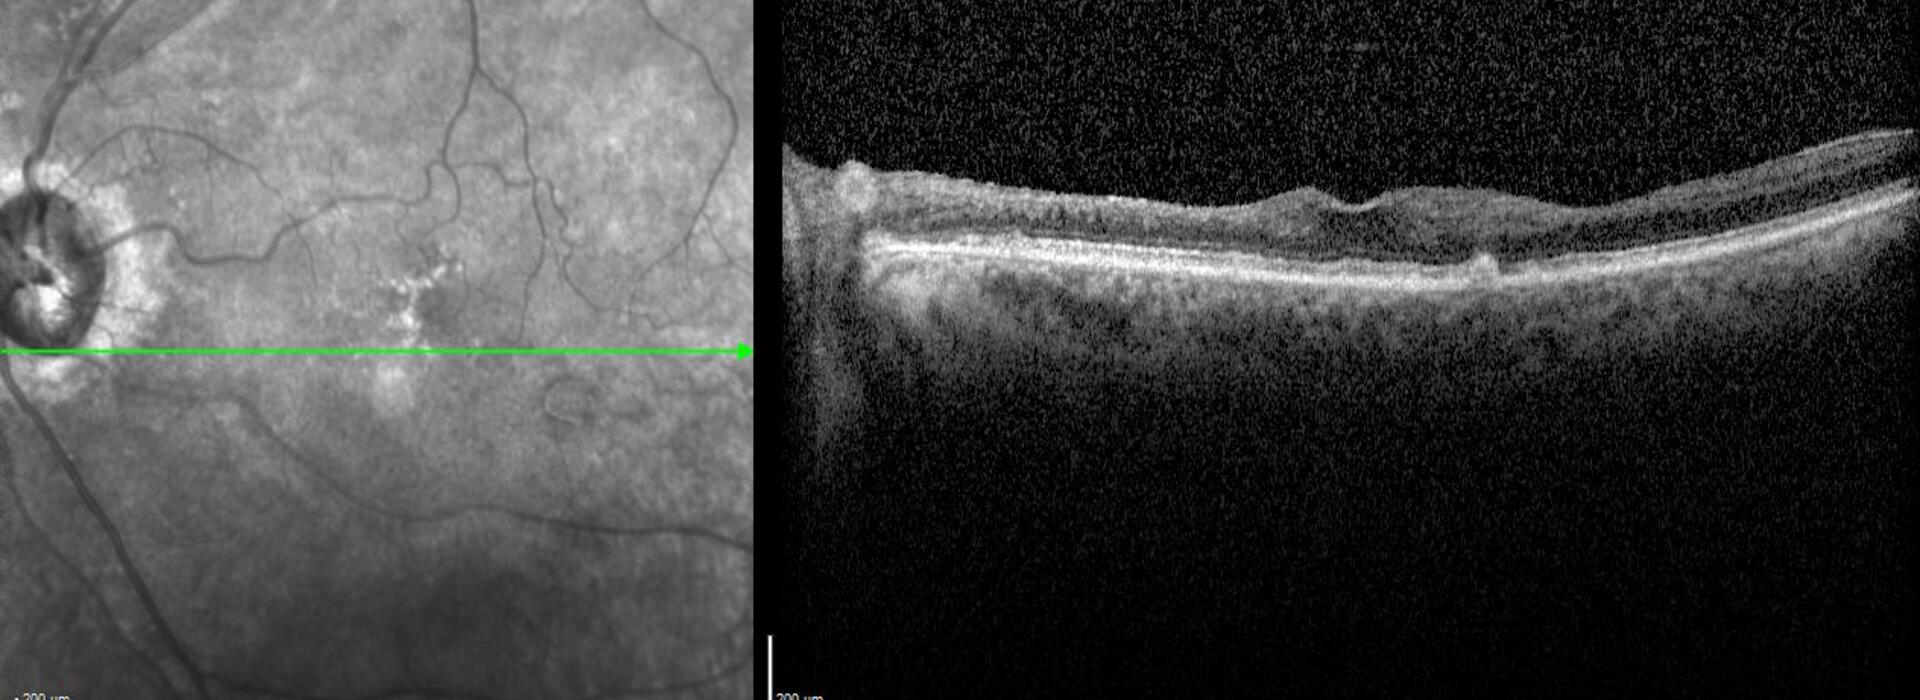

SIGNOS CLAVE EN ISQUEMIA COROIDEA

El Dr Pedro Fernández revisa la circulación retiniana y coroidea normal, y describe mediante imagen multimodal las alteraciones estructurales que aparecen cuando se comprometen las ramas arteriales que irrigan la coroides. La identificación de estos signos es esencial, ya que están presentes en patologías urgentes. Reconocerlos de forma temprana permite orientar el diagnóstico y optimizar el manejo para evitar secuelas visuales irreversibles.